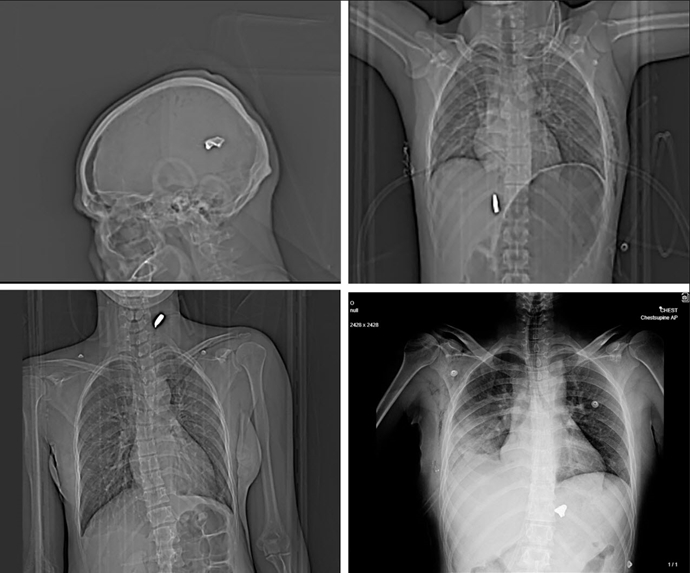

در میان تصاویر، موارد متعددی از جراحات تهدیدکننده جان دیده میشود. اسکن مردی جوان با نام مستعار «وحید»* گلولهای کالیبر بالا را نشان میدهد که در گردن او گیر کرده و نای بهدلیل خونریزی و تورم شدید به سمت راست منحرف شده است. در موردی دیگر، تصویر سیتیاسکن یک مرد میانسال وجود گلولهای معلق در مغز و حباب بزرگ گاز در داخل جمجمه را نشان میدهد؛ آسیبی که به گفته کارشناسان پزشکی «احتمالاً غیرقابل بقا» است. در بدن دو مرد جوان دیگر نیز گلولههای کالیبر بالا در نزدیکی ستون فقرات مشاهده شده است.

در یکی از موارد، تصویر قفسه سینه مردی به نام «علی»* وجود بیش از ۱۷۴ ساچمه فلزی را در حفره سینه راست نشان میدهد. به گفته کارشناسان، تراکم ساچمهها حاکی از شلیک از فاصله بسیار نزدیک است. ریه راست او دچار فروپاشی شده و با وجود جراحی فوری، خطر مرگ او بسیار بالاست.

کارشناسان بالستیک همچنین گلولههای یافتشده در بدن ۹ بیمار دیگر را از نوع «تمام فلزی» (Full Metal Jacket) تشخیص دادهاند که با سلاحهای تهاجمی کالیبر ۷.۶۲ مانند AK-47 مطابقت دارد؛ سلاحهایی که به گفته تحلیلگران توسط سپاه استفاده میشود. یکی از این کارشناسان گفته است: «این نوع جراحات معمولاً در میدان جنگ دیده میشود؛ شلیک چنین سلاحهایی به سمت مردم به معنای قصد کشتن است.»